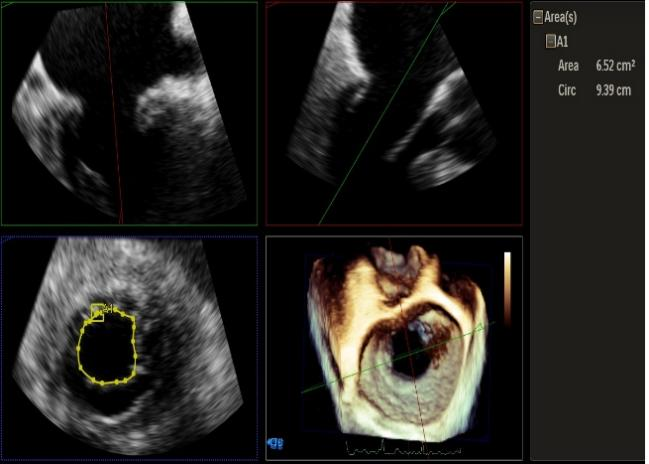

Qlab软件勾画估测瓣口面积约:6.52cm²